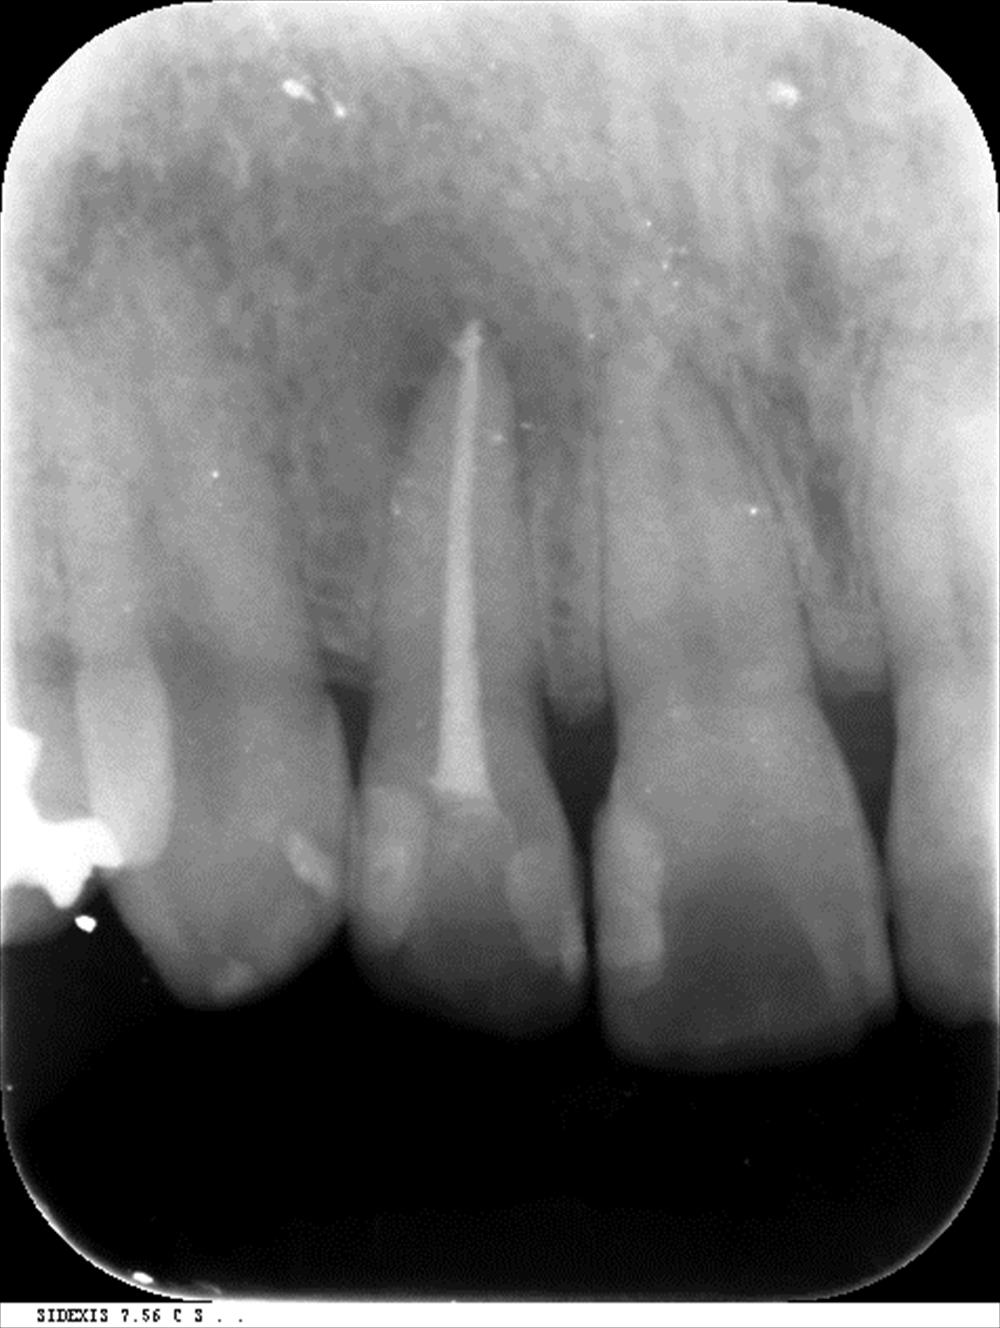

2回目で根管充填。症状もなくなりました。

この方は精密根管治療の方。1回目

歯茎がやはり膿んでいます。虫歯って放っておくと大変な事になります。ここまで進行すると骨から飛び出してきます。匂いの原因になる事も。